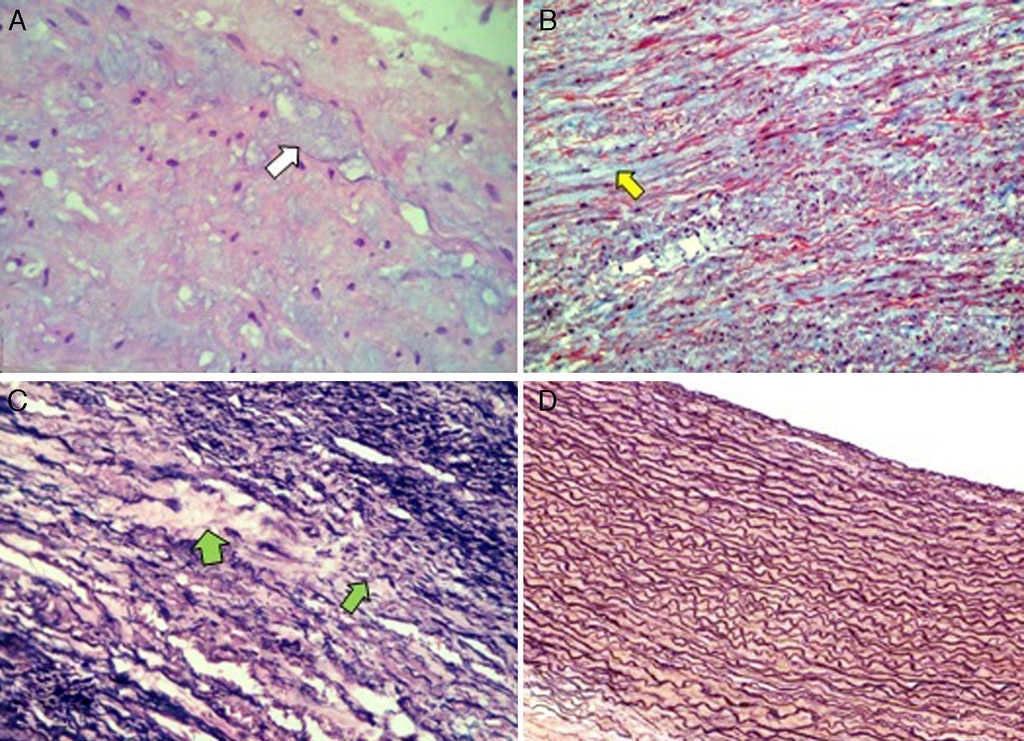

Por histología se demostró en la capa media arterial presencia focal de incipientes zonas quísticas con material basófilo (fig. 2A); la tinción con tricrómico de Masson exhibió depósito de colágena tipo I intersticial en las zonas afectadas, lo que podría traducir procesos de daño y reparación3 8 9 (fig. 2B) como se ve en la cardiopatía congénita y en la HP 3 5. La tinción de van Gieson mostró trama de fibras elásticas, con disrupción multifocal de las mismas en el espesor de dicha capa (fig. 2C).

Figura 2 Microfotografía de la pared del aneurisma de la arteria pulmonar. 2A: se aprecian zonas basófilas de aspecto quístico en el intersticio (flecha blanca). H&E 40x. 2B: depósito intersticial de colágena tipo 1 en las zonas de reparación (flecha amarilla). Tinción de tricrómico de Masson 25x. 2C: fibras elásticas rotas y adelgazadas con depleción secundaria de las mismas (flechas verdes). Tinción de plata de van Gieson 40x. 2D: comparación con fibras elásticas intactas en arteria pulmonar normal. Tinción de plata de van Gieson 10x.

Al aneurisma de la AP se le ha definido como una dilatación permanente y circunscrita del tronco de la AP > 4 cm de diámetro y 3 cm para sus ramas derecha e izquierda5 6. Los principales hallazgos histológicos son fragmentación y disminución de las fibras elásticas con degeneración de la capa media, incremento en las fibras de colágeno y disminución de las células musculares lisas3 8 9. Sin embargo, algunos autores han reportado histología normal de la pared aneurismatica4 (fig. 2D).